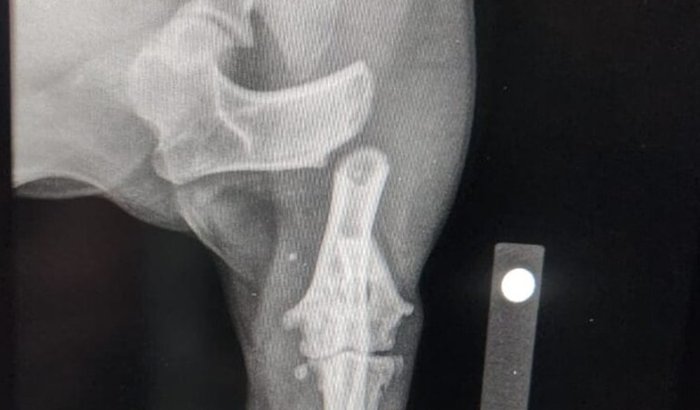

A Cachorrinha Lua, foi atropelada e teve a patinha quebrada, ela precisa passar por uma cirurgia e o valor fica R$ 4.000,00. No momento estamos sem condições de bancar esse valor. Conseguimos fazer a radiografia na Clinica Pet Help de Carapicuiba, que por sinal e excelente.